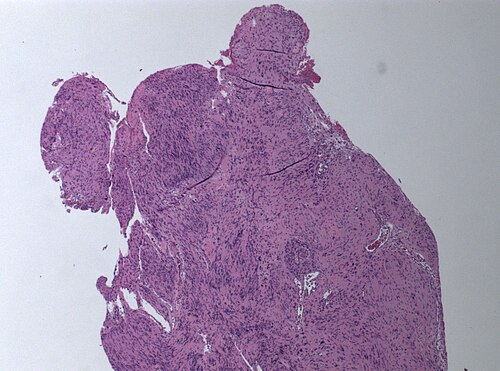

49 year old woman. Sudden hearing loss of the left side.

Cerebellopontine angle. Low magnification. H&E stain.

Schwannoma, WHO grade I.

Comment: This is the most frequent tumor of the cerebellopontine angle. Positive S-100 Immunostain and reticulin around individual tumor cells confirm the diagnosis and rule out a potential meningioma.